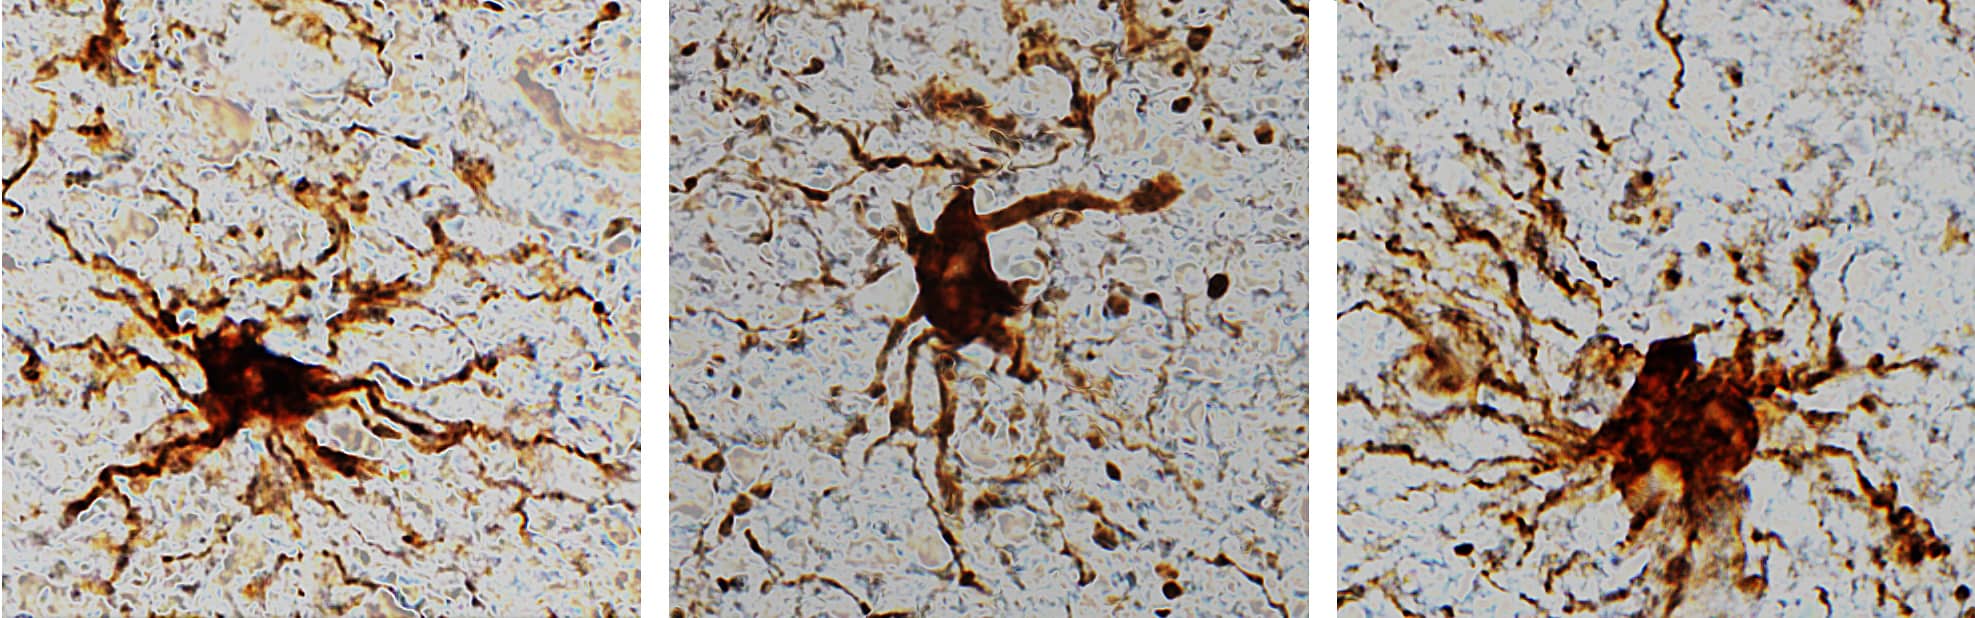

لكنهم لاحظوا قدراً كبيراً من النشاط الذي يحدث في جيناتٍ خاصة بالخلايا الدبقية، إذ استمرّت الخلايا الدبقية بالنموّ لساعاتٍ بعد الموت، ونمت منها أطرافٌ تشبه الذراع. الخلايا الدبقية هي خلايا التهابية تحافظ على التوازن، وتشكّل مادة "النخاعين" الدهنية التي تحيط بالمحور العصبي لبعض الخلايا العصبية في الجهاز العصبي المحيطي، وتدعم الخلايا العصبية وتحميها.

قال الدكتور جيفري لوب، رئيس قسم طب الأعصاب في جامعة إلينوي: "إن حقيقة تضخم الخلايا الدبقية بعد الموت ليس مفاجئاً للغاية نظراً لأنها خلايا التهابية، وتتمثل مهمتها الأساسية في إعادة الدماغ إلى وضعه الطبيعي بعد إصاباته بالحرمان من الأوكسجين أو السكتة الدماغية. لكن المثير للدهشة هو الآثار المحتملة التي تتضمنها الدراسة".